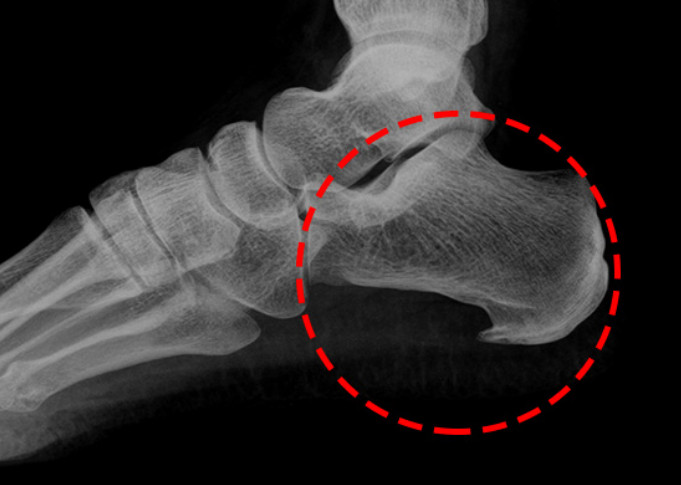

족저근막염은 발바닥 뒤꿈치에 염증이 생기면서 나타나는 통증을 말합니다. 남성보다 여성에게 약 2배 정도 더 많이 발생한다고 하며, 과도한 발의 스트레스나 무리한 운동이 주요 원인으로 알려져 있습니다. 이 밖에도 급격한 체중 증가나 평발 역시 발병 위험을 높이는 요인이 됩니다.

족저 근막염의 가장 흔한 증상은 아침에 통증이 특히 심하다는 점입니다. 밤사이 수축된 족저근막이 아침에 첫 발을 디디며 갑자기 늘어나 통증이 생기기 때문입니다. 대개 종아리 근육이 짧아지면서 발바닥 근막이 당겨져 발생하는 경우가 많습니다. 따라서 예방을 위해서는 평소 종아리와 발바닥을 함께 관리하는 것이 중요합니다. 이미 증상이 있다면 생활습관 개선과 더불어 필요에 따라 약물이나 의료적 치료를 병행해야 합니다.